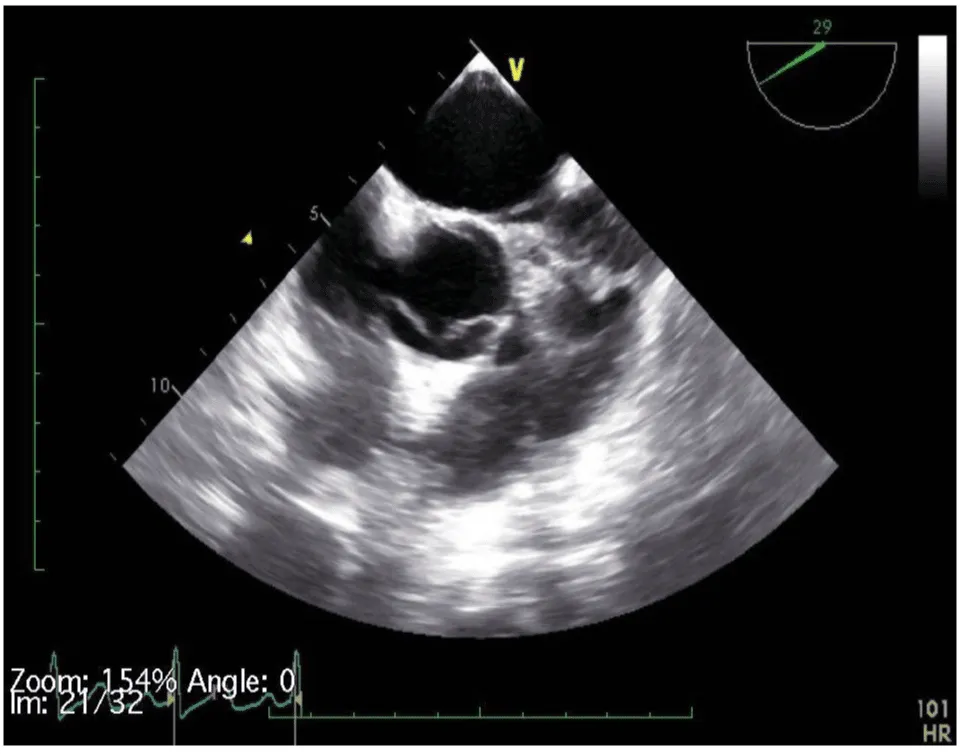

Her initial vital signs upon presentation to the hospital were; blood pressure: 161/76 mm Hg, heart rate: 96 beats per minute, respiratory rate: 27 breaths per minute. Physical exam revealed a cardiac auscultation findings of a grade 2 diastolic murmur which was loudest at the 2nd right intercostal space as well as a grade 2 systolic flow murmur. Cardiac biomarkers were elevated with initial troponin-I of 0.33 ng/mL, peak of 2.28 ng/mL and subsequent down trend. Electrocardiography (Figure 1) showed sinus rhythm with anterior and inferolateral T wave inversion and chest radiograph (Figure 2) was unremarkable. She underwent coronary angiography which revealed normal coronary arteries. The takeoff of the right coronary artery (RCA) was noted to be superior and anterior to its normal position (Figures 3A and 3B). Transthoracic and transesophageal echocardiography (TEE) revealed normal left ventricular systolic function and severe insufficiency of the aortic valve with Quadricuspid morphology (Figure 4A in Diastole, Figure 4B in Systole, Figure 4C Long Axis of the aortic valve). She underwent aortic valve replacement with a # 19mm ON-X mechanical valve. Intraoperatively it was noted that the ostium of the right coronary artery was over the aberrant leaflet. Her postoperative course was complicated by the development of supraventricular tachycardia, posteriorly localized pericardial effusion, severe hemolytic anemia, renal failure and pancreatitis leading to her death eleven days after the surgery.

Figure 4a: QAV in diastole (arrows pointing to 4 cusps).

Figure 4b: QAV in systole.

Figure 4c: Long Axis of the aortic valve demonstrating severe aortic Insufficiency.

The diagnosis of QAV was facilitated by TEE, which revealed the characteristic findings. The short axis views of the aortic valve are optimal for making the diagnosis of QAV. The classic X shaped commissural aortic valve pattern in diastole (Figure 4B) compared to the Y shape of a trileaflet valve is diagnostic (Figure 4D) [3].